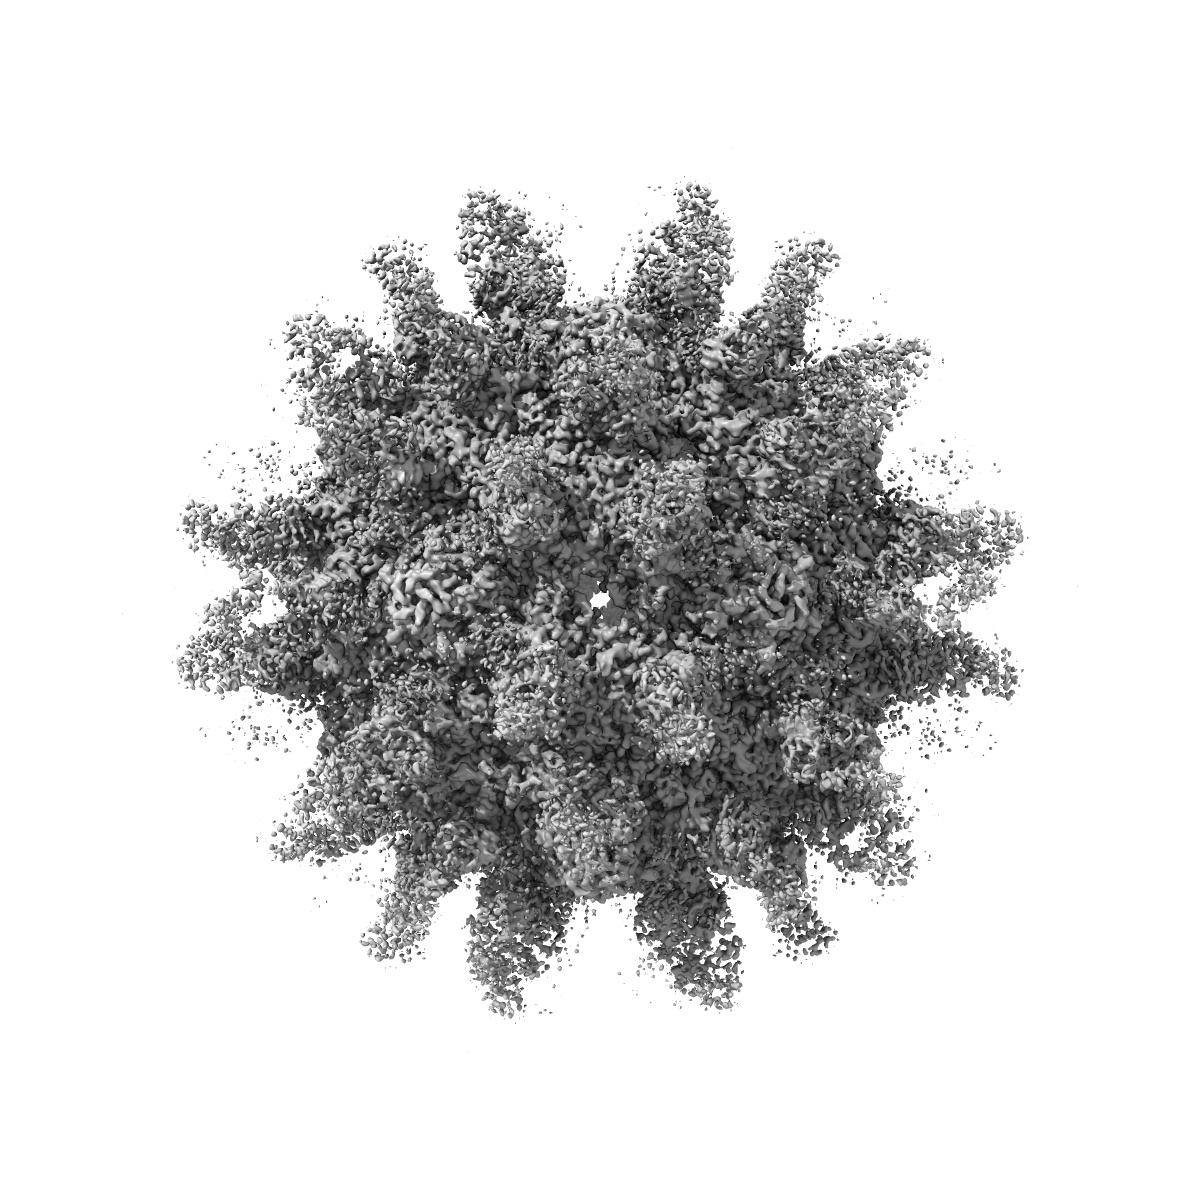

Cryo-EM structure of Coxsackievirus B1 empty particle in complex with nAb 9A3 (classified from CVB1 mature virion in complex with 8A10 and 9A3)

Single-particle3.82 Å